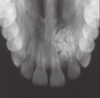

-30-40s, angle of mandible -unilocular (13%) or multilocular (classic) -soap bubble appearance with root resorption

What is the presentation of unicystic ameloblastoma?

-younger patients (20s), posterior mandible (38/48) impacted/unerupted, asymptomatic and well circumscribed unilocular radiolecency.